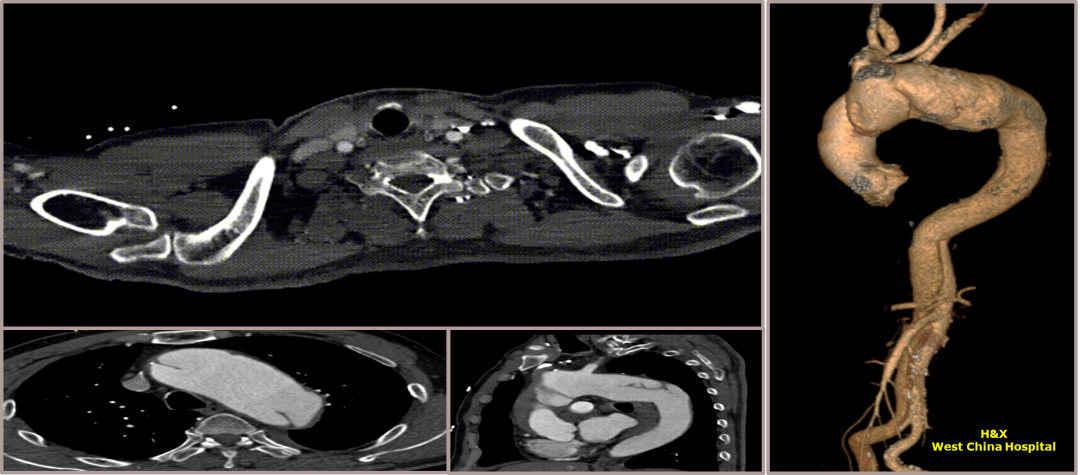

夹层动脉瘤CTA:A型主动脉夹层术后残余主动脉弓部夹层,头臂干及左颈总动脉根部夹层累及,向下累及胸腹主动脉至髂血管平面。

术前影像

夹层动脉瘤CTA:主动脉夹层(非A非B型),累及主动脉弓至腹腔干发出平面以上腹主动脉,真腔小,假腔大;主动脉弓及左颈总动脉、左锁骨下动脉近端管径增粗,合并壁内血肿